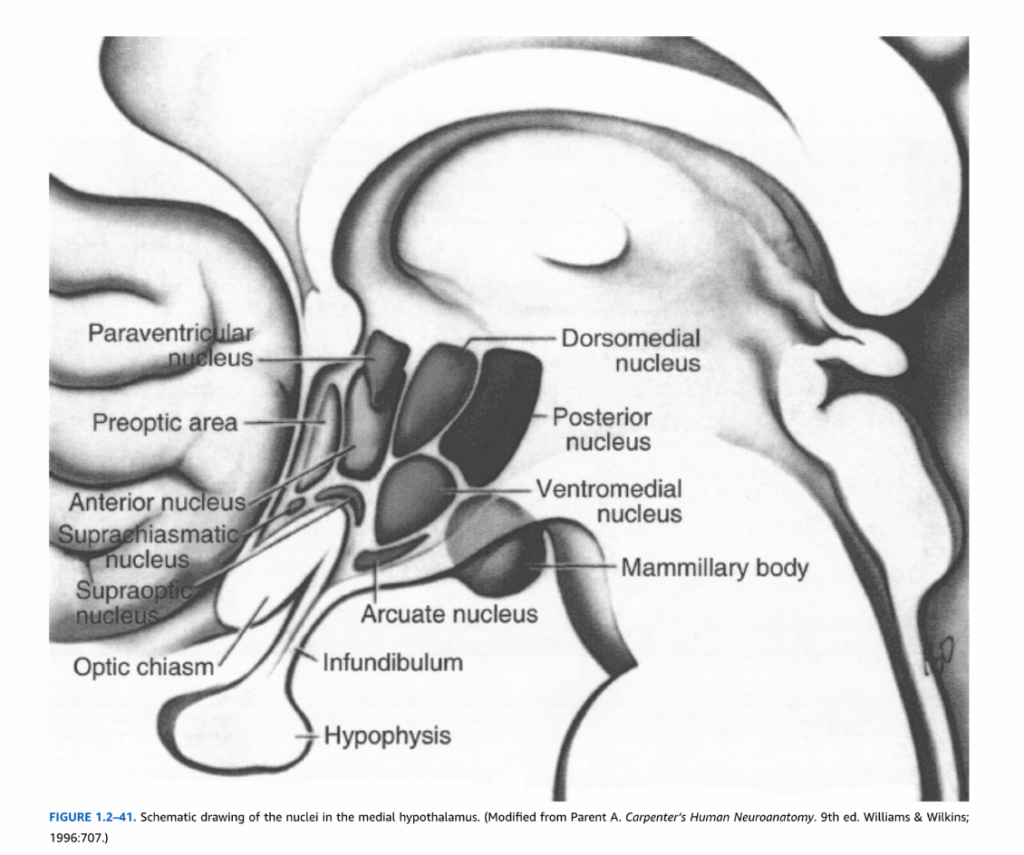

視床下部

視床下部は、間脳内の小さな構造で、情動だけでなく自律神経系、内分泌系、および一部の体性機能を調節する神経回路の重要な構成要素である。辺縁系の他の構成要素との関係に加えて、脳幹と脊髄の様々な内臓および体性核と相互接続し、下垂体の機能を調節する出力を提供する。

その下面において、視床下部は前方を視神経交叉、後方を乳頭体の後縁によって境界づけられる。これら2つの構造の間の視床下部の領域は灰白隆起と呼ばれ、正中隆起を生じ、これは漏斗柄、次に下垂体後葉と連続している(図1.2-41)。これらの特徴に基づいて、視床下部は前方から後方に3つの区域に細分される:視索上部、漏斗部、乳頭体部。(さらに、視索上部の直前に位置する終脳構造である視索前野は、通常、視床下部の一部と考えられている。)これら3つの区域もまた、視床下部体を通って乳頭体に向かう脳弓によって、各側で内側と外側の領域に分けられる。表1.2-4に示されているように、視床下部の6つの部分は異なる核を含んでいる。

これらの異なる核は、視床下部の多様な機能を媒介している。視交叉上核は網膜からの直接的および間接的投射を受け、日周リズムの調節において重要である。視索上核と室傍核は、オキシトシン含有線維とバソプレシン含有線維を下垂体後葉神経部に送る大型細胞(大細胞ニューロン)を含んでいる。さらに、室傍核の一部のニューロンは正中隆起に投射し、そこで副腎皮質刺激ホルモン放出因子などの神経ペプチドを門脈血系に放出する。これらの神経ペプチドは、前葉下垂体ホルモンの合成と放出を制御する。室傍核はまた、延髄と脊髄の交感神経および副交感神経自律神経領域を調節する下行投射も生じる。

図1.2-41. 内側視床下部の核の模式図。(Parent A. Carpenter’s Human Neuroanatomy. 9th ed. Williams & Wilkins; 1996:707より改変。)